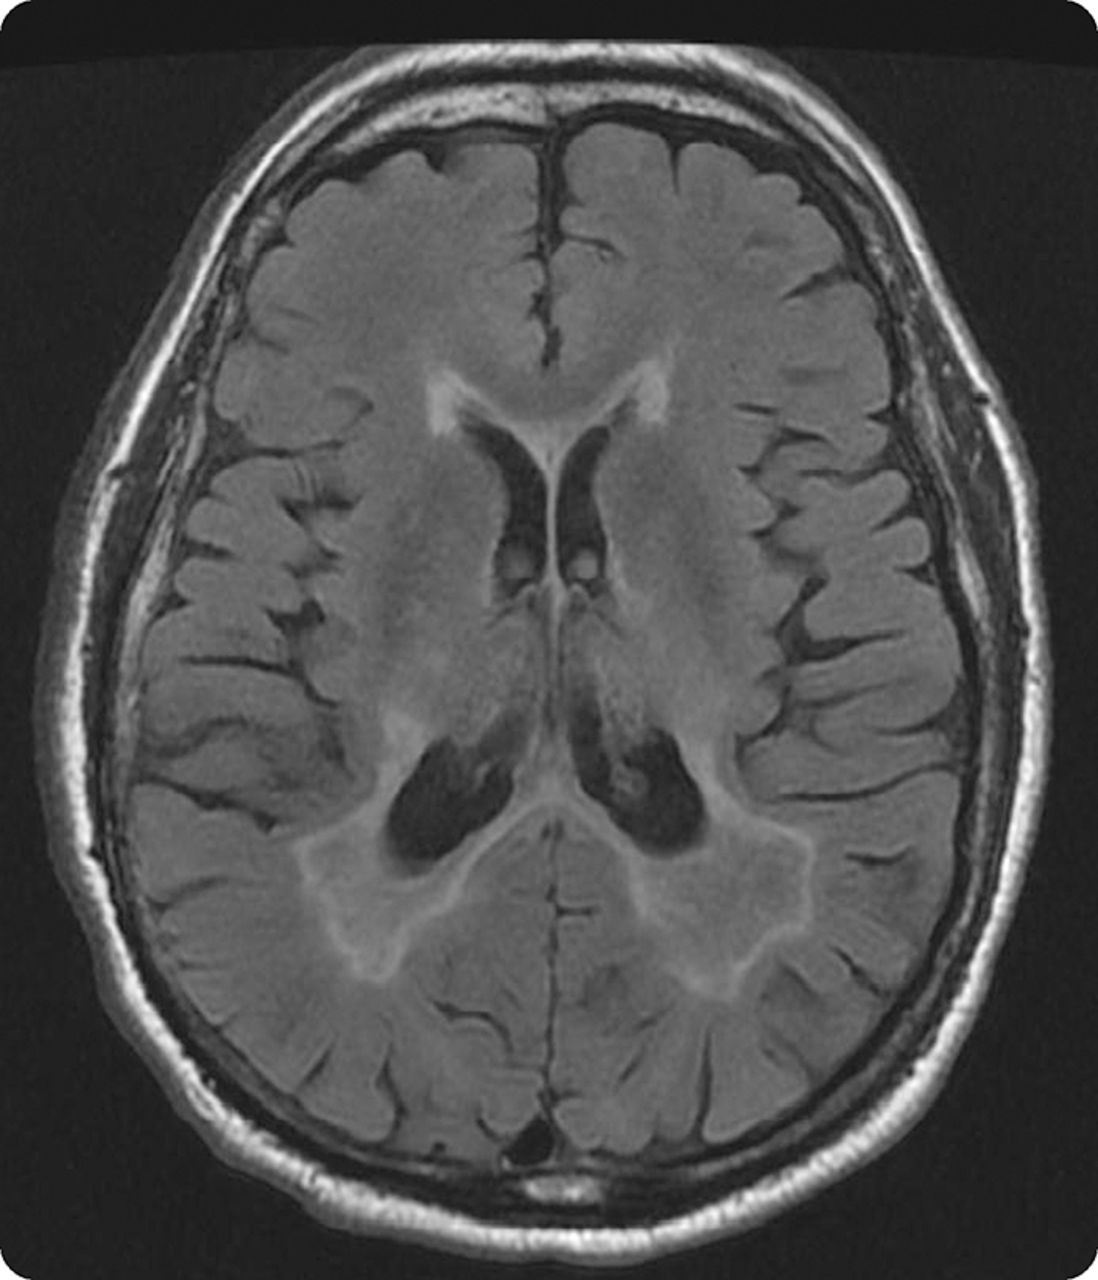

71岁的慢性吸烟者有一个11个月的历史单眼双目椭圆眼球震颤和振动幻视紧随其后(视频首页Neurology.org)。大脑MRI显示广泛的室周的T2信号变化(图)和脑脊液蛋白升高到102 mg / dL。脑脊液和血清中多种面板显示血清浓度升高anti-P / q型电压门控钙通道(VGCC)和anti-neuronal-type电压门控钾通道抗体。后一个潜在的恶性肿瘤未找到一个广泛的调查。病人与卡马西平治疗有症状的控制,其次是第四大剂量甲强龙,导致温和改善。Anti-VGCC抗体已经涉及多种的眼球震颤和小细胞肺癌是最常见的恶性肿瘤有关。1,2